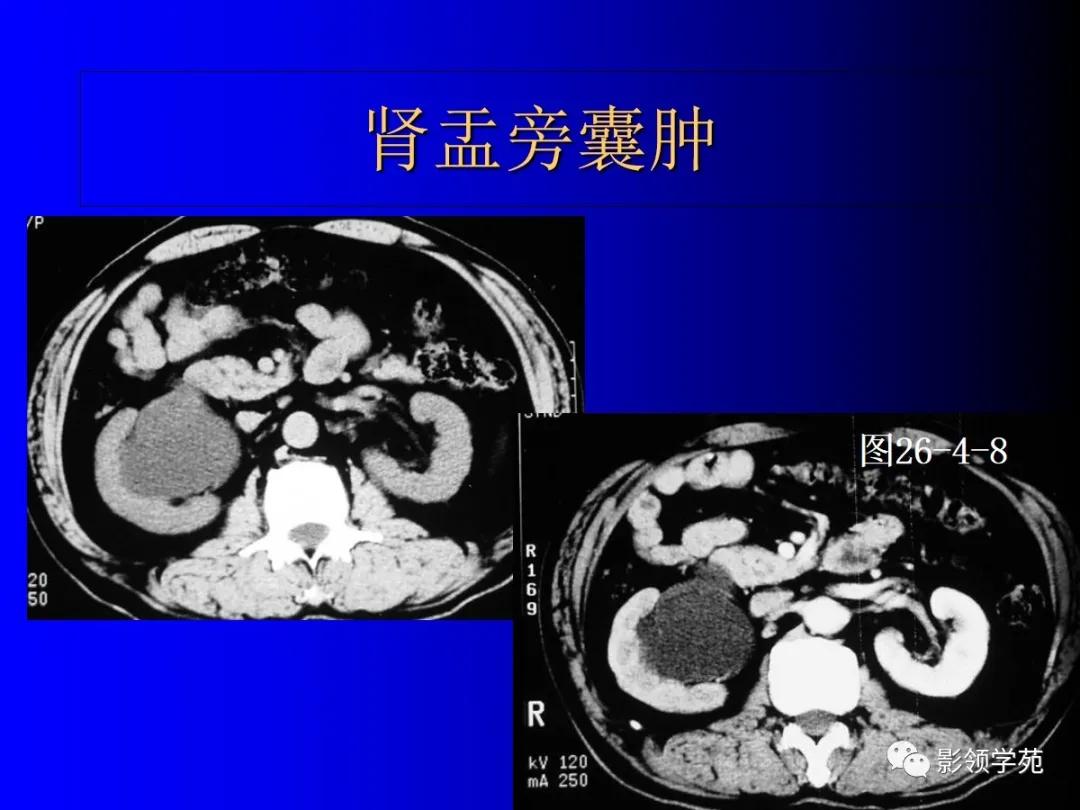

5、肾盂旁囊肿(肾窦囊肿)

观点1:是一种含清亮尿液的尿囊肿或淋巴液体的假性囊肿,不与集合系统相通。呈圆形,位于肾窦旁,可单发,也可双侧多发。增强扫描无强化。

观点2:纯属解剖概念,大部分仍为单纯性肾囊肿。